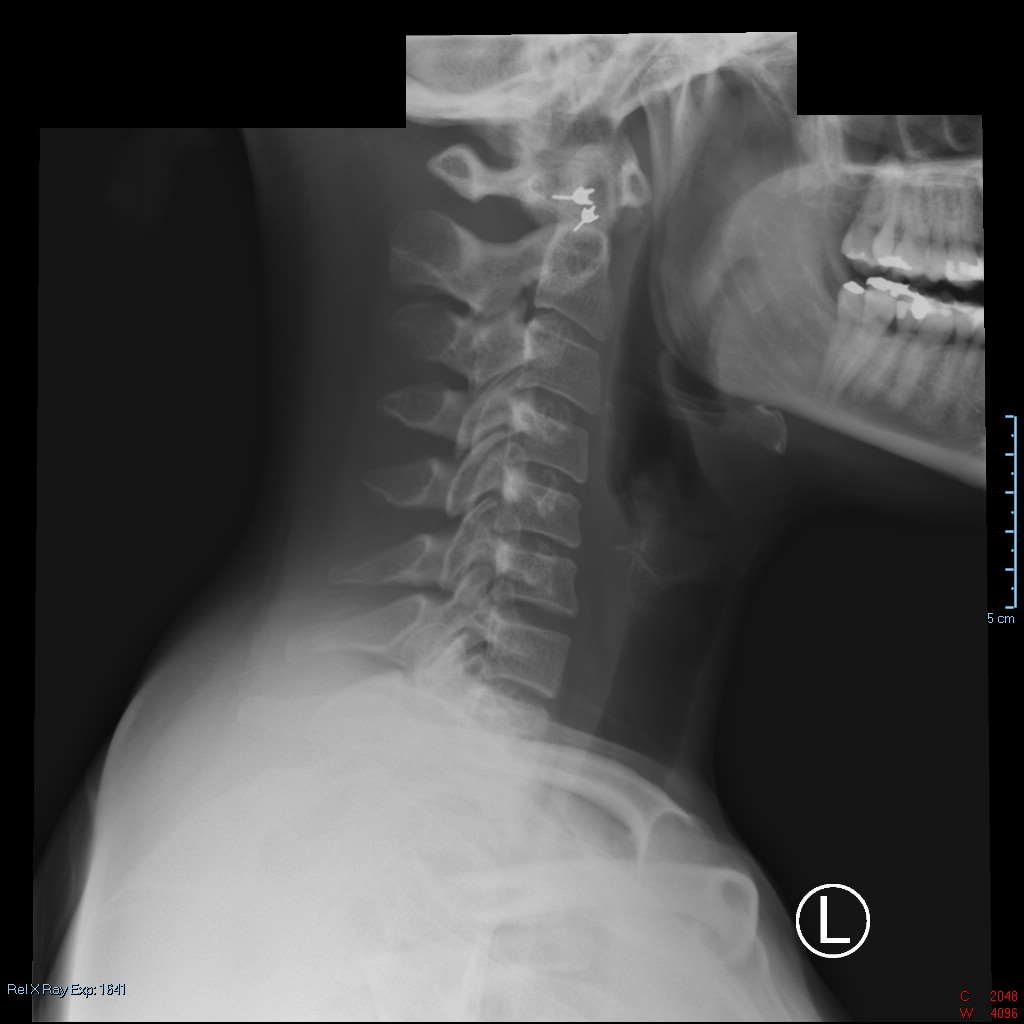

From drmarks.com

Digital Xrays for Chiropractic Treatment Chiropractor Orange CA What Error Is Unique To Digital X Rays Digital radiography is based on capturing and storing the radiograph using discrete (digital) values 1 as opposed to. On digital imaging systems, an exposure indicator provides useful feedback to the radiographer about exposures. Problems not directly associated with the digital detector system can also be manifested in the image. Figure 4 shows image artifacts caused by a metal filter in. What Error Is Unique To Digital X Rays.